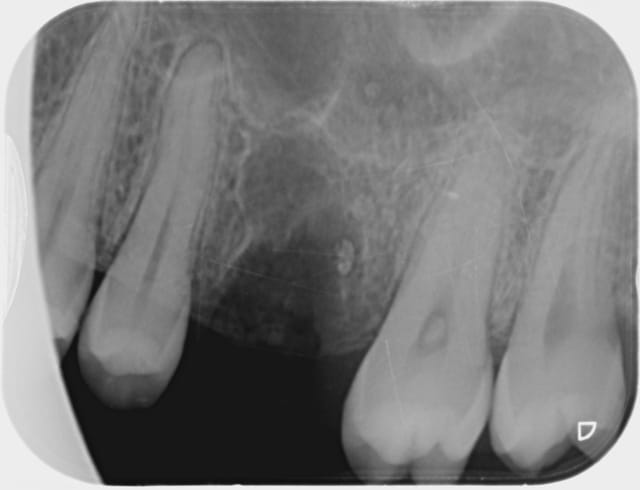

J'ai accueilli cette patiente un peu phobique , fait une anesthésie , une avulsion , un curetage de l'alvéole qui contenait de la pâte canalaire , le tout avec application de façon à ne pas pénétrer le sinus , vérifier une possible CBS , et suturer le tout .